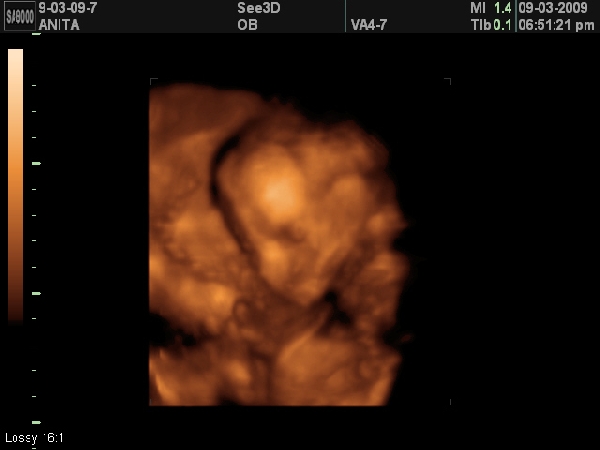

Voltunk 4D uh-n 2 hete és tök elkeseredtem, mert azt mondta az uh-s doki, hogy picit megint rossz helyen van a placenta, bár hál'Istennek nincs a méhszáj közelében. De azért zavar, mert múltkor már jó helyen tapadt én meg felbuzdulva mászkáltam egy csomót és most megint fekhetek, hogy jó helyre kerüljön.

Legközelebb 4D-re a 30. hetes uh-n megyek, így árpilis 15-re kaptunk időpontot.

Amúgy nagyon kis cuki volt Áron baba először nem akarta megmutatni magát, aztán megkértem, hogy forduljon meg és meg is tette rögtön.

Amin még kiakadtam, hogy a jobb veséjében találtak valami minimális kamrai tágulatot, de azt mondták, hogy ilyen kicsi 10-ből 9 terhességnél előfordul és szülésre elmúlik, no para! De azért egy kicsit mégis aggaszt.

Ráadásul még a lepényemen is találtak egy nagyon kicsi cisztát, amitől szintén kiborultam, de azt mondta, hogy ez is fel fog szívódni és összességében minden rendben.